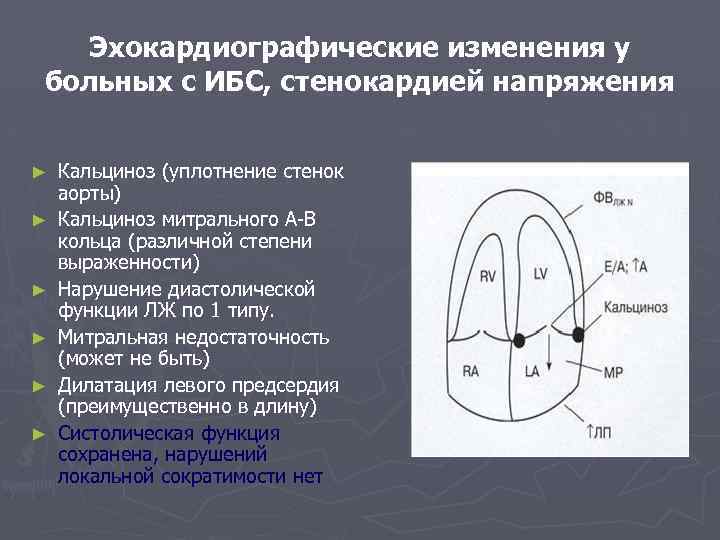

Эхокардиографические изменения у больных с ИБС, стенокардией напряжения ► ► ► Кальциноз (уплотнение стенок аорты) Кальциноз митрального А-В кольца (различной степени выраженности) Нарушение диастолической функции ЛЖ по 1 типу. Митральная недостаточность (может не быть) Дилатация левого предсердия (преимущественно в длину) Систолическая функция сохранена, нарушений локальной сократимости нет